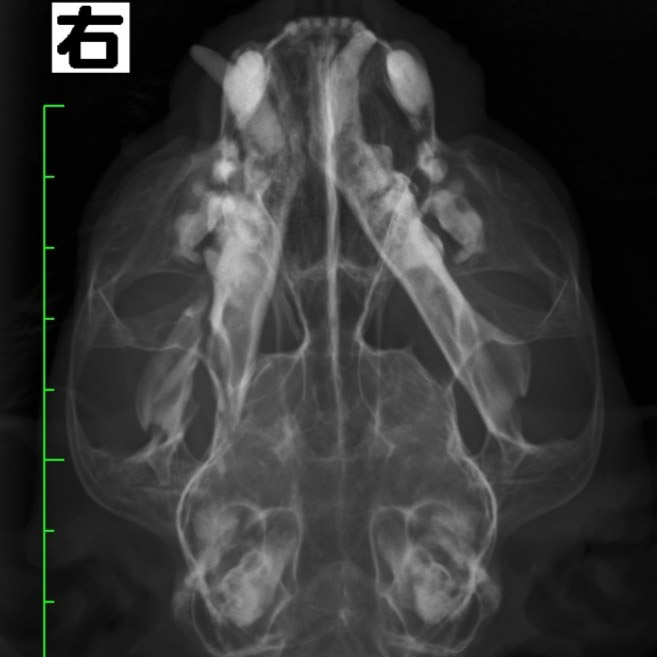

下顎骨骨折

雑種猫(14歳)

犬に咬まれた

手術前

手術後

CT横